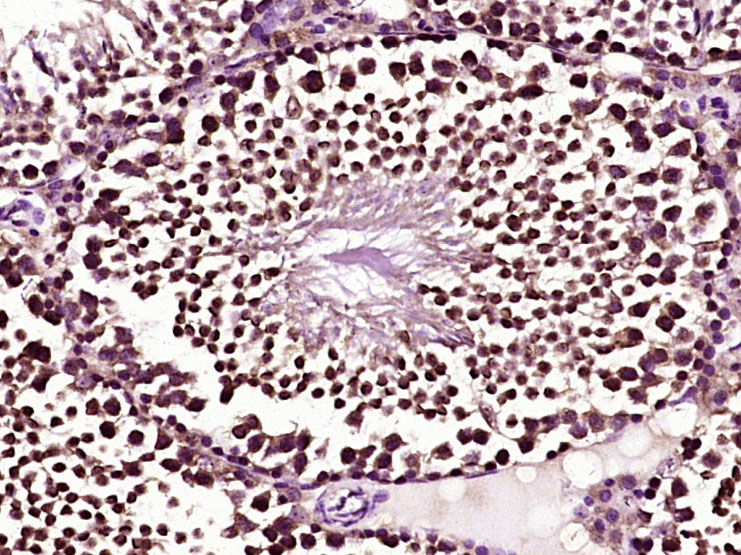

Paraformaldehyde-fixed, paraffin embedded (mouse testis tissue); Antigen retrieval by boiling in sodium citrate buffer (pH6.0) for 15min; Block endogenous peroxidase by 3% hydrogen peroxide for 20 minutes; Blocking buffer (normal goat serum) at 37°C for 30min; Antibody incubation with (Bcl-xL) Polyclonal Antibody, Unconjugated (bs-1336R) at 1:400 overnight at 4°C, followed by operating according to SP Kit(Rabbit) (sp-0023) instructionsand DAB staining.